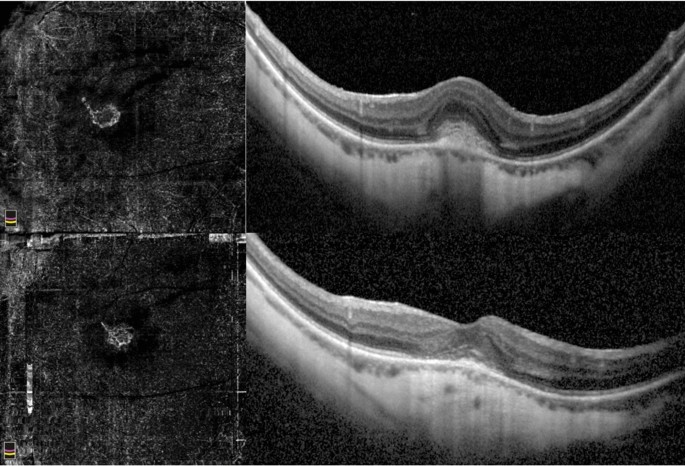

Myopic CNV was categorized either as subfoveal or juxtafoveal/extrafoveal according to the location. Moreover, mCNV was categorized, using OCTA according to previously described classifications, either as immature (small-size, disorganized vascular loops without an evident interlacing vascular network), or mature (larger, highly structured, characterized by an interlacing pattern of the new vessel network with a large CNV select area) (Figs. 1 and 2, respectively)25. Subretinal fibrosis was defined as the fundoscopic detection of greyish or yellowish subretinal tissue underneath the retina in the foveal or parafoveal area, corresponding to an OCT image of a well-demarcated hyperreflective lesion situated between the retinal pigment epithelium and the neurosensory retina.

Mature myopic CNV. Baseline OCTA examination of a case of mature myopic CNV (top left) with wide subretinal hyperreflective exudation with fuzzy borders and absence of fluid accumulation signs assessed by SD-OCT (top right). The neovascular network at the final visit (12 months) after 5 intravitreal injections assessed by OCTA is still visible and shows a slight reduction of the size (bottom left). The SD-OCT exudation signs are regressed with absence of intraretinal cysts and subretinal fluid (bottom right).